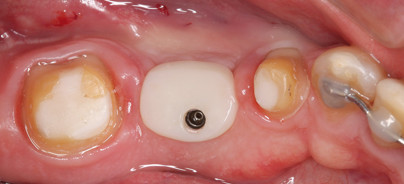

Für Suprakonstruktionen im Molarenbereich ist den höheren kaufunktionellen Belastungen Rechnung zu tragen, um technisch bedingte Komplika­tionen zu vermeiden. Konfektionierte Abutments weisen im Seitenzahnbereich eine starke Abweichung von der Form eines beschliffenen natürlichen Pfeilers auf, sodass die ausgeprägte anatomische Gerüstgestaltung erschwert wird. Anfänglich wurde die Anwendung von oxidkeramischen Kronen für Implantatsuprastrukturen dadurch ­limitiert, dass eine ausgeprägte anatomische Gerüstmodellation nicht oder nur sehr schwer möglich war. Die Folge waren Gerüststrukturen, die insbesondere im approximalen Bereich eine unzureichende Unterstützung der Verblendkeramik boten und daher bereits nach sehr kurzer Zeit zu einem Versagen der Verblendkeramik führten. Individuell gefertigte vollkeramische Aufbauten, die bereits die Geometrie eines beschliffenen Prämolaren oder Molaren nachbilden, sind unter dem Gesichtspunkt einer ana­tomisch korrekten Gerüstgestaltung entsprechend vorteilhafter. Zembic et al. (2009) untersuchten in einer randomisierten Studie das klinische Verhalten von metallkeramischen und vollkeramischen Kronen im Eck- und Seitenzahnbereich über einen Zeit­raum von drei Jahren. Im Rahmen dieser Studie wurden individuelle Titanaufbauten mit metallkeramischen Kronen versorgt, während die individuellen Zirkonoxidaufbauten mit vollkeramischen Kronen auf Aluminium­oxid- oder Zirkonoxidbasis versorgt wurden. Nach einer dreijährigen Beobachtungszeit zeigten beide Versorgungsformen eine Überlebenswahrscheinlichkeit von 100 Prozent, es konnte keine Gerüst- oder Verblendkeramikfraktur beobachtet werden. Aus diesen Ergebnissen kann gefolgert werden, dass die technische Komplikationsrate von vollkeramischen Suprakonstruktionen durch die Verwendung von individuellen Vollkeramik­abutments reduziert werden kann, sodass sich ihre Anwendung insbe­sondere für Einzelkronen im Mola­ren­bereich empfiehlt. Unter klinischen Gesichtspunkten ist für die Gestaltung eines optimalen Durchtrittsprofils die verstärkte Ausformung der Weichgebe im Molaren­gebiet erforderlich. Da die Form von konfektionierten Heilungskappen oder Gingivaformern stark vom Durchtrittsprofil eines Molaren abweicht, können hier mit individuell geformten

Heilungskappen verbesserte Weichgewebsverhältnisse geschaffen werden. Für die Herstellung des individuellen Heilungsaufbaus kann zum Beispiel der Einbringpfosten des Implantates gekürzt und dann bereits bei der Frei­legung individuell mit lichthärtendem Kunststoff ergänzt werden, sodass eine rechteckiges bis ovales Durchtrittsprofil erzeugt wird (Abb. 7 und 8).